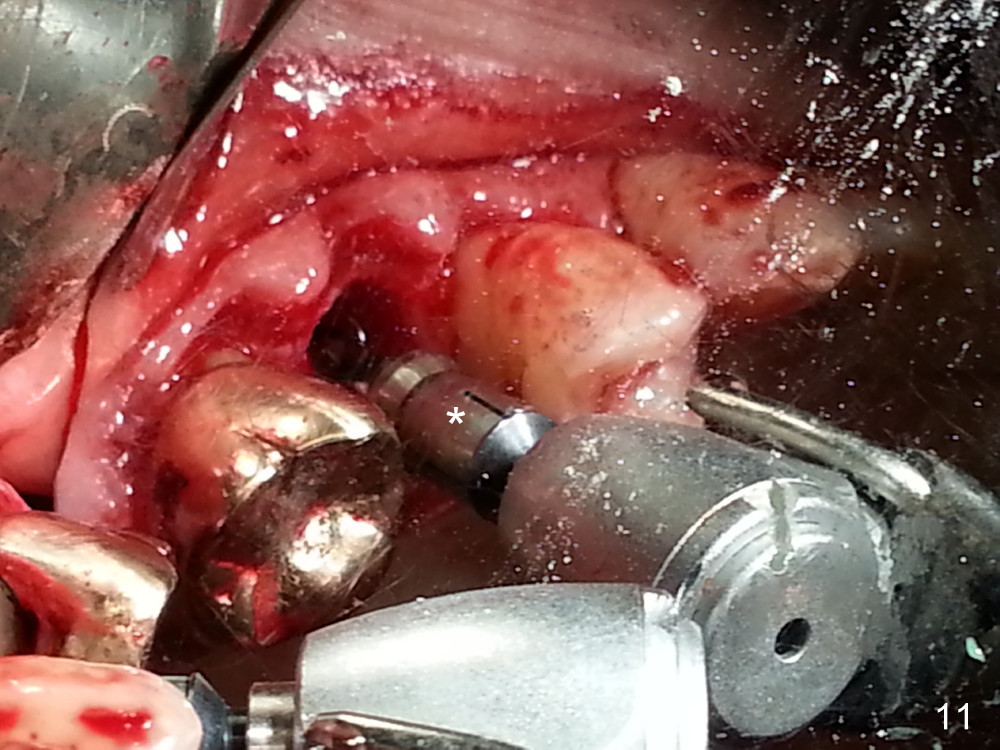

Grafting Following Immediate Implant (Photos Provided by Xue Steven, DDS)

The tooth #13 appears to be affected by periodontits and occlusal trauma (Fig.1*). After using a periotome (Fig.2), the tooth is extracted (Fig.3). The buccal flap is raised (Fig.4). Gingival graft is to be harvested from the site of #15 (Fig.5). The tissue is elevated buccally (Fig.6) and separated (Fig.7). The donor site is covered by a collagen membrane (Fig.8*). A diamond bur is used to induce bleeding from the socket (Fig.9*). Osteotomy is initiated (Fig.10) and enlarged (Fig.11,12). A tapered implant is being placed (Fig.13-15) following internal sinus lift (Fig.16,17). The implant is placed subcrestally, followed by bone graft (Fig.18), soft tissue graft (Fig.19), and suturing (Fig.20 <, Fig.21).